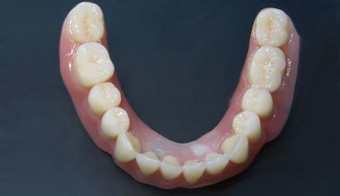

Próteses móveis sobre Implantes

Soluções protéticas móveis estabilizadas sobre implantes.

Prótese móvel estabilizada por sistema de bola.

Prótese móvel estabilizada por sistema de barra.